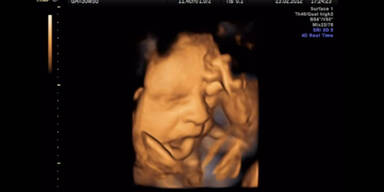

Dass Babys bereits im Mutterleib gähnen, konnte zum ersten Mal auf Bilder gebannt werden.

Es war bereits bekannt, dass Föten ihren Mund öffnen und schließen, trotzdem wollten die Wissenschaftler der Diskussion um das pränatale Gähnen ein Ende setzen und rückten mit einem hochauflösenden Ultraschall einem schwangeren Bauch auf die Pelle. Daraus enstanden süße Bilder.